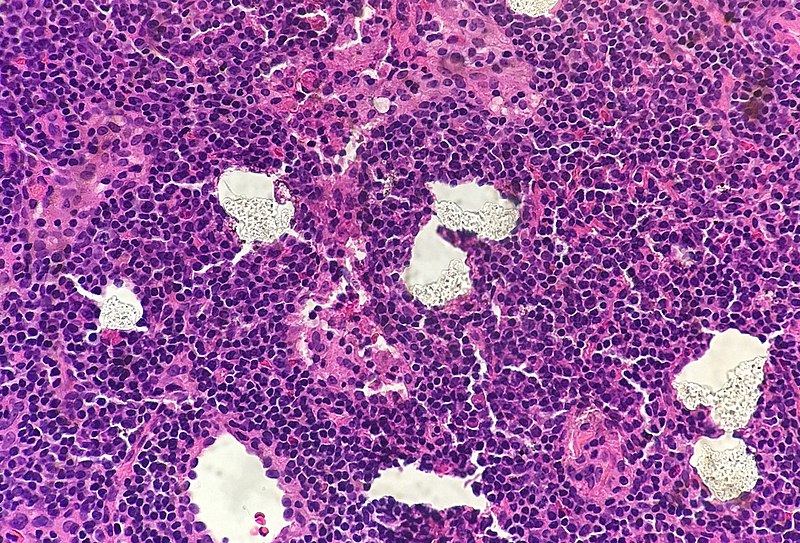

Arthritic changes – Arthritis is related to a condition of painful joints due to inflammation or swelling. A type of arthritis is rheumatoid arthritis, it is an autoimmune disease where the immune system attacks the joints, starting with the lining of joints. Rheumatoid arthritis is heavily related to lung problems, about 80% of arthritic patients have lung-related issues, making it the second leading cause of death with rheumatoid arthritis patients. Rheumatoid arthritis caused lung problems are most commonly extra-articular i.e., outside of the joints and involves pulmonary nodules; damage to the lung airways, pleural effusion and interstitial lung disease. In rheumatoid arthritis associated interstitial lung disease the auto-immune system gets over active and attacks the lungs and causes scarring. With time, the scarring build-up leads to difficulty breathing and reduced lung function.